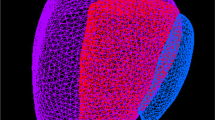

Zonal anatomy

We found 18 different types of very heterogeneous and unclear terminologies of zonal anatomy (Fig. 3, Additional file 1: Fig. S1). Out the 33 articles reviewed, less than 1/4 (8/33) [23, 25, 32, 34, 36, 37, 40, 43] provided precise terminology and segmentation protocol. Frequently the inappropriate term “central gland” (CG) was used, with ambiguous definition of central zone (CZ) and anterior fibro-muscular stroma (AFMS) alternatively included in peripheral zone (PZ) or transition zone (TZ), or mainly not described at all. Two studies mis-used the term “central zone” to refer to the “central gland” [27, 39].

Schematic of the four major types of protocol of zonal segmentation. Type A: articles for which “central gland” included CZ, TZ and AFMS. Type B: articles for which “central gland” included TZ and CZ. No details for AFMS. Type C: articles which did not provide details for AFMS, CZ or CG. CZ seemed to be mostly segmented PZ, while AFMS seemed to be mostly segmented with TZ, usually called “CG”. Type D: articles which did not provide details for AFMS or CZ. CZ and AFMS seemed to be mostly segmented with PZ. CZ central zone, TZ transition zone, AFMS anterior fibro-muscular stroma, PZ peripheral zone, CG central gland